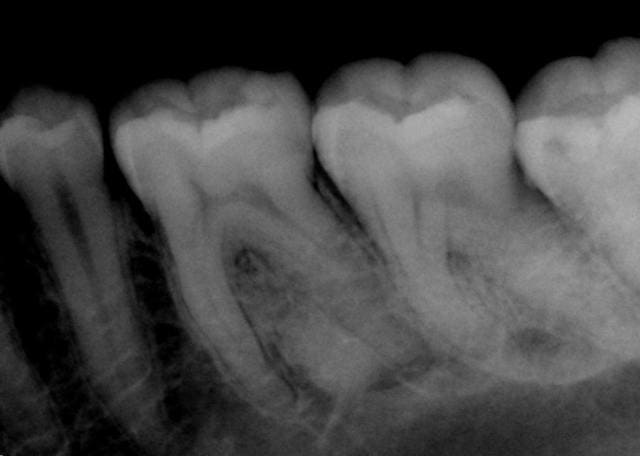

Sinon on devine, tartre mesial de 38, poche paro debutante, carie email 36 distal 38 mesial a confirmer par une belle btw...

Ensuite une radio apicale orthocentree permettra de mieux definir l image radiodense au niveau de la racine de 36.

La 38 semble semi-incluse ?

Tartre 37-38

La 38 est utile ? Si non, exo, si oui tx paro et suivi

J'ai revu la patiente, toujours douleurs plus ou moins importantes dans ce secteur.

36 réagit à la percussion, test au froid positif.

Rien de particulier à la pano, juste cette image osseuse bizarre.

Pensez-vous qu'un cbct puisse apporter plus ?